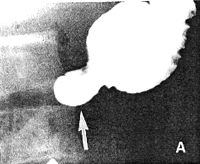

In 52 of the 100 patients the swallowed, liquid barium suspension passed rapidly down the oesophagus, traversed the stomach and flowed through the pyloric aperture in one smooth movement, without any delay or hold-up at the pylorus. This occurred in the absence of visible motor movements in the stomach. In many cases the head of barium was in the duodenum while the tail end was still in the oesophagus (Fig. 12.1). In all cases the normal, deep annular indentation of the pyloric ring between the stomach and duodenum became clearly visible as soon as the barium had traversed the aperture (Fig. 11.1). The part of the stomach on the immediate oral side of the ring (the pyloric sphincteric cylinder) was expanded without being unduly distended.

![]() |

| Fig. 12.1. Rapid swallowing in fasting stomach. Barium suspension traverses pyloric aperture, which is patent (arrow). Tail end of barium still in oesophagus. Absence of gastric motor movements |